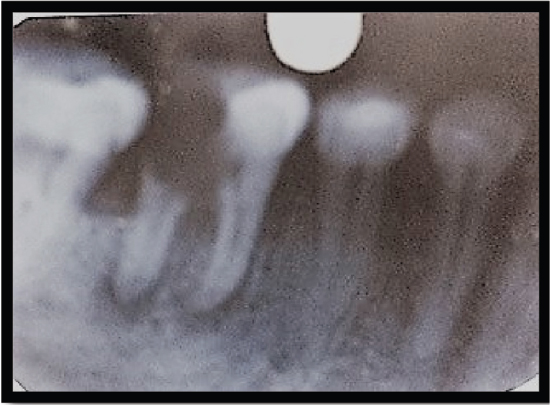

Medical College Faculty of Dental Sciences, Lucknow, with the complaint of pain in the left mandibular first molar (36) for 2-3 days. On examination, the tooth was found to be grossly carious [Figure 1]. The past medical history, as well as the past dental history of the patient, was nonsignificant. On radiographic examination, radiolucency was present in the distal root [Figure 2]. The mesial root was completely intact, but furcation was involved. It was decided that the distal root should be hemisected after the completion of endodontic therapy. Endodontic therapy was initiated with respect to the mesial root and completed in a single sitting. Canal cleaning and shaping were completed using 3% sodium hypochlorite (Septodent, France) along with 15% EDTA (Glyde, Dentsply, Tulsa, USA) and rotary file system Revo S (Micro-Mega, France). Obturation was performed by cold lateral compaction of gutta-percha [Figure 3]. Distal root hemisection was performed with a vertical cut method. The crown was cut with a tapered fissure carbide bur till the furcation was reached. After separation of both roots, the distal half was extracted [Figure 4]. The empty socket was thoroughly irrigated, and the flap was sutured. The patient was recalled for 1 month and evaluated for the healing of the extraction socket. After complete healing of the extraction socket, biomechanical preparation of the molar and premolar crown was done [Figure 5]. The reduced molar resembled a premolar in shape. A temporary bridge was seated during the healing and consolidation phase to prevent the drifting of the remaining root. Definitive restoration therapy was accomplished 6 weeks after hemisection [Figure 6]. A two-unit porcelain fused metal fixed partially replaced the distal root of the mandibular first molar and retainers on the second premolar and remaining part of the mandibular first molar. The interdental spaces are contoured so that hygiene can be accomplished with toothbrushes.

Figure 2. IOPAR showing radiolucency